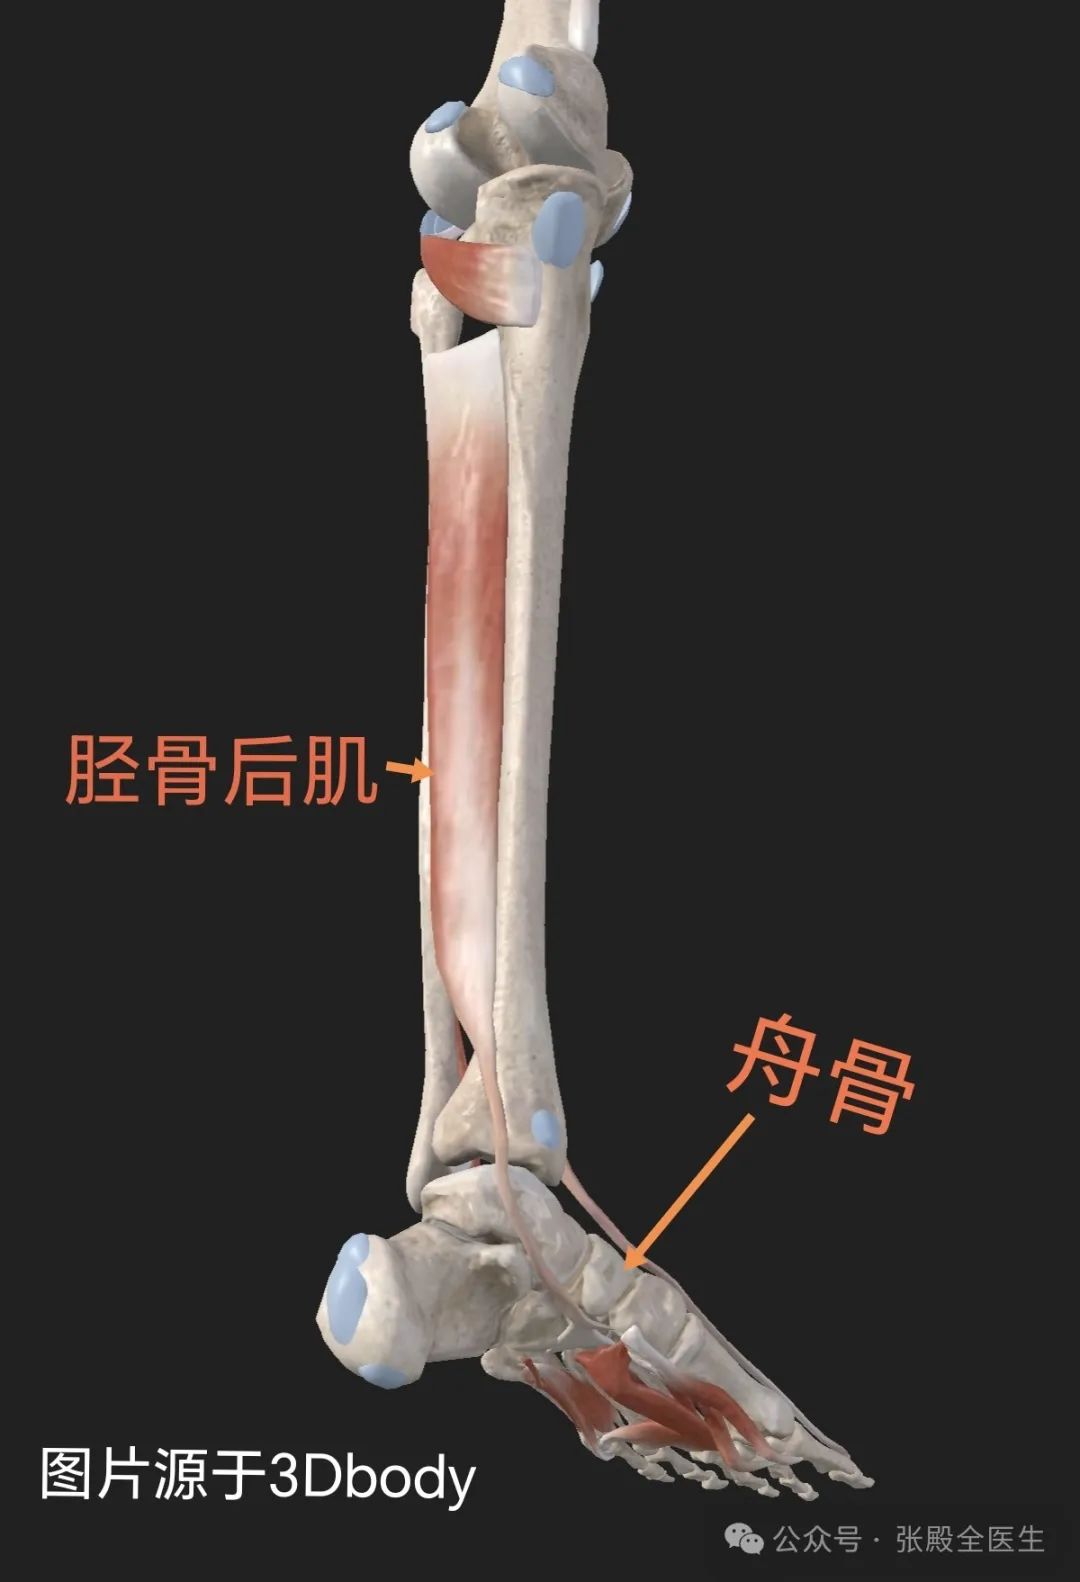

副舟骨(Accessory Navicular Bone)是一个先天性骨变异,主要位于内侧舟骨的后方,通常被认为是一种附加骨。并不是每个人都有这种骨骼,大约5%到15%的人群可能会存在副舟骨。对于大多数人来说,副舟骨不会引起任何问题,但在一些情况下,它可能会导致疼痛和其他不适症状。副舟骨的分型通常依据其形态和与舟骨的连接方式进行分类,目前最广泛使用的是Geist分型,分为三种类型:

I型副舟骨(籽骨型):

副舟骨呈圆形或卵圆形,小而圆,位于胫后肌腱内,相当于胫后肌腱内的籽骨。与舟骨之间没有直接接触,与其分开最大可达5毫米。占副舟骨的30%,通常无症状。

II型副舟骨(假关节型):

呈三角形或心形,大小约10-12mm。通过1-2毫米厚的纤维软骨或透明软骨与舟骨相连,形成微动关节。约占副舟骨的50-60%,最终可能会与舟骨骨性融合。

III型副舟骨(角型舟骨):

副舟骨与舟骨体已融合,关节面消失,形成延长的弧形舟骨。被认为是II型副舟骨的融合型,由于在骨性突起上形成疼痛,偶尔会出现症状。

副舟骨若无临床症状的患者不需治疗。有临床症状如疼痛者,早期应给予保守治疗,包括口服药物、物理治疗。如有扁平足,配用专用鞋垫等。当保守治疗无效,也可考虑手术治疗。具体治疗方式需专业医师评估。